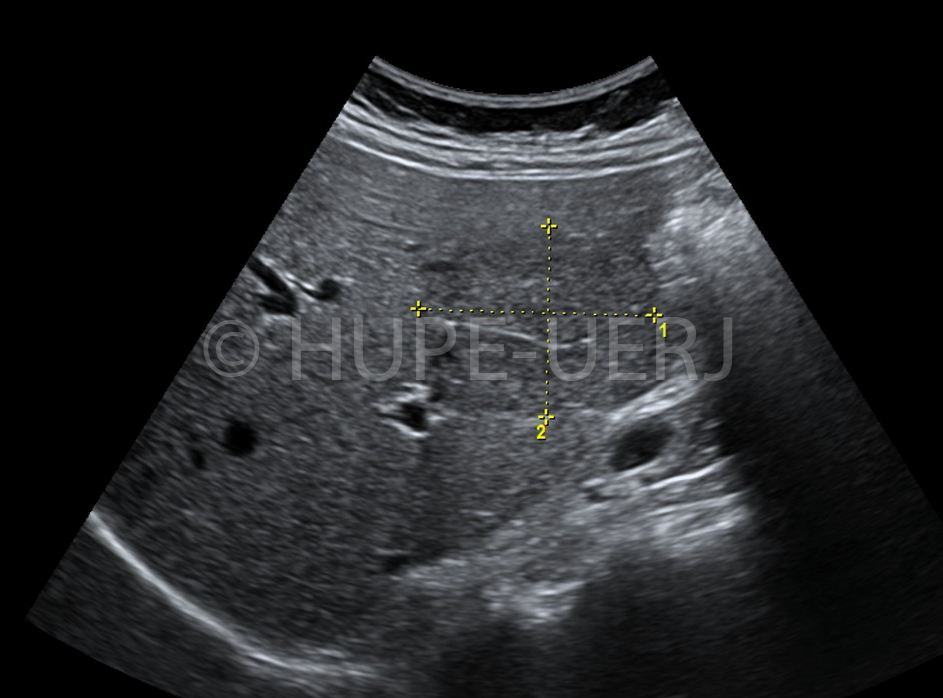

O achado ultrassonográfico característico é de massa

hiperecogênica ovóide localizada no quadrante inferior direito, com um apêndice

de características normais. Sua limitação é a de ser operador dependente. A TC é

Setas apontam imagem em halo na projeção do omento maior que corresponder ao infarto deste tecido